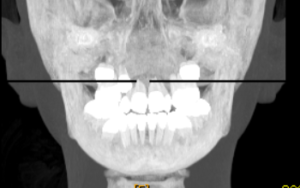

「上顎犬歯埋伏のCT画像」

川崎歯科(大阪府吹田市)